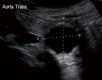

CTA of a 65-year-old gentleman who presented to the emergency department with hypotension and abdominal and back pain. (A) Axial image demonstrating peri-aortic stranding and hematoma at the level of the renal arteries (white arrow); (B) more distal axial image of the same patient in (A) with peri-aortic hematoma extending into the retroperitoneal space (white solid arrow), consistent with a ruptured AAA. The aneurysm sac measures 6.5 cm (white dashed arrow). CTA, computed tomography angiography; AAA, abdominal aortic aneurysms.